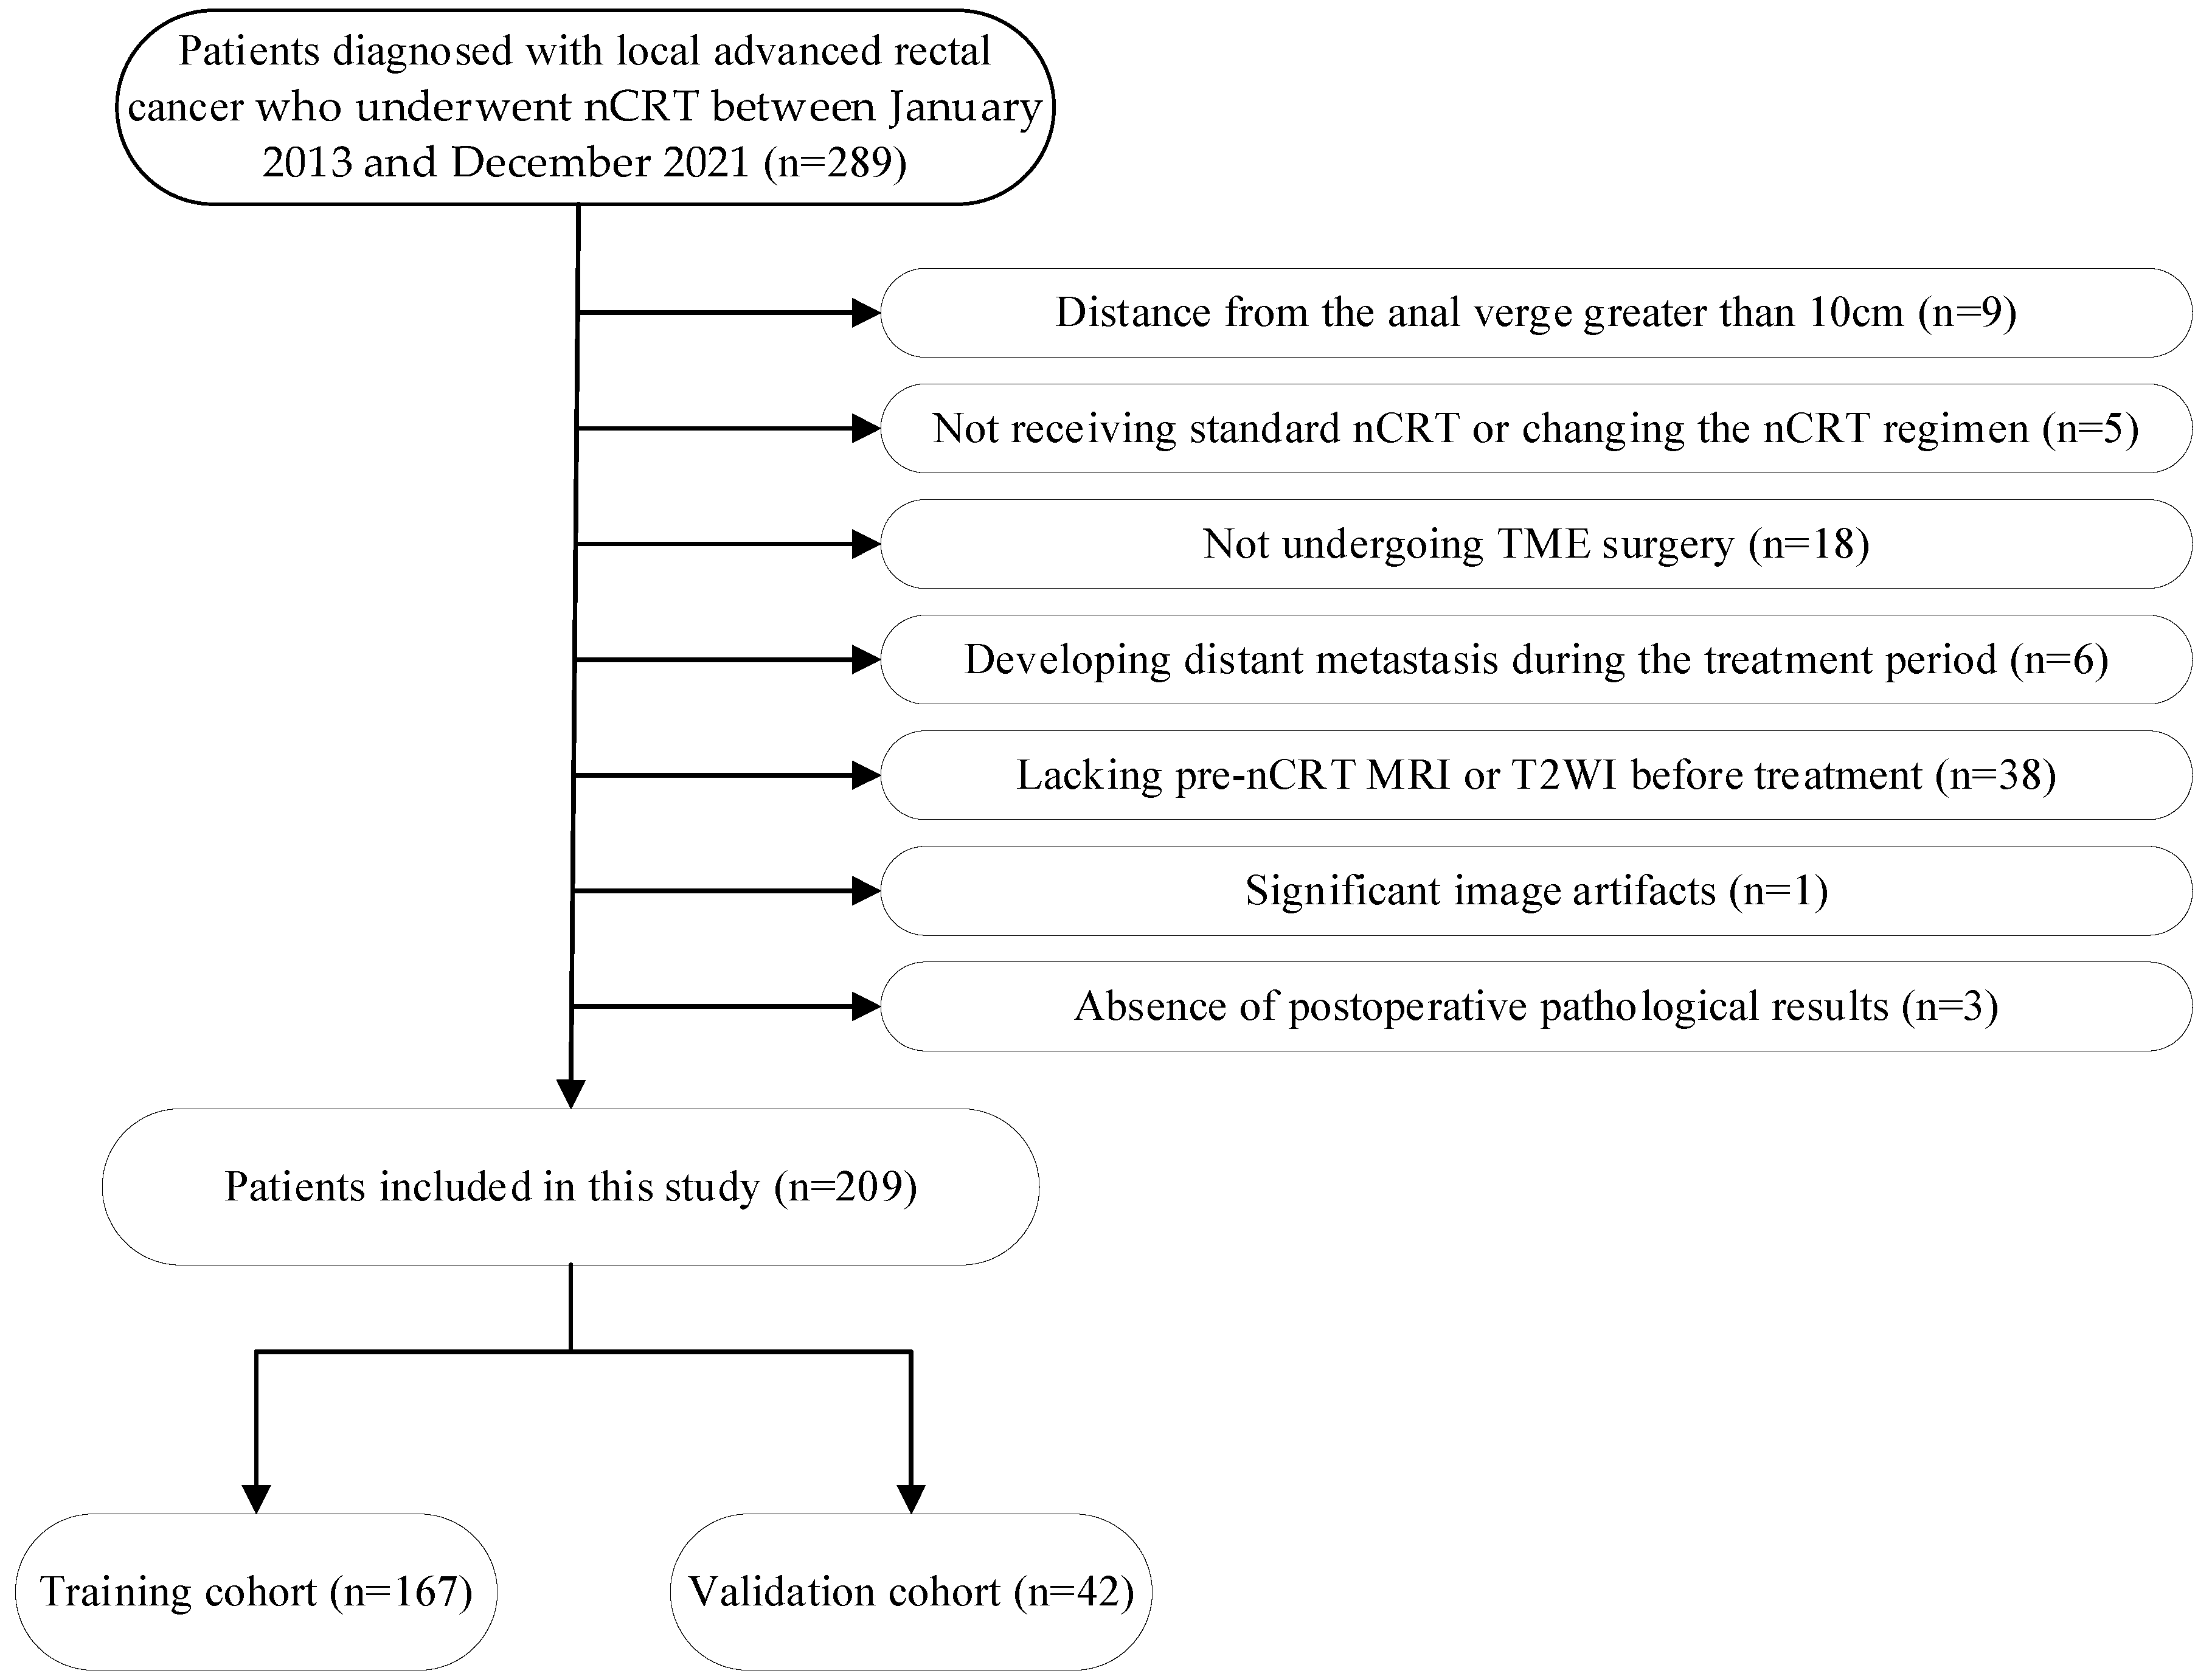

2.1. Study Patients

3.1. Clinical Features